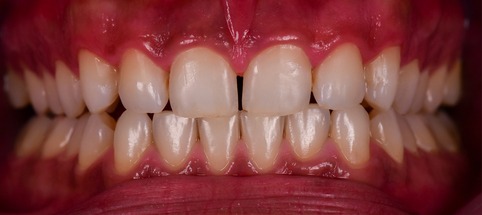

A 26-year-old female with severe crowding. Comprehensive orthodontic treatment was completed. Patients were amazed by the results.